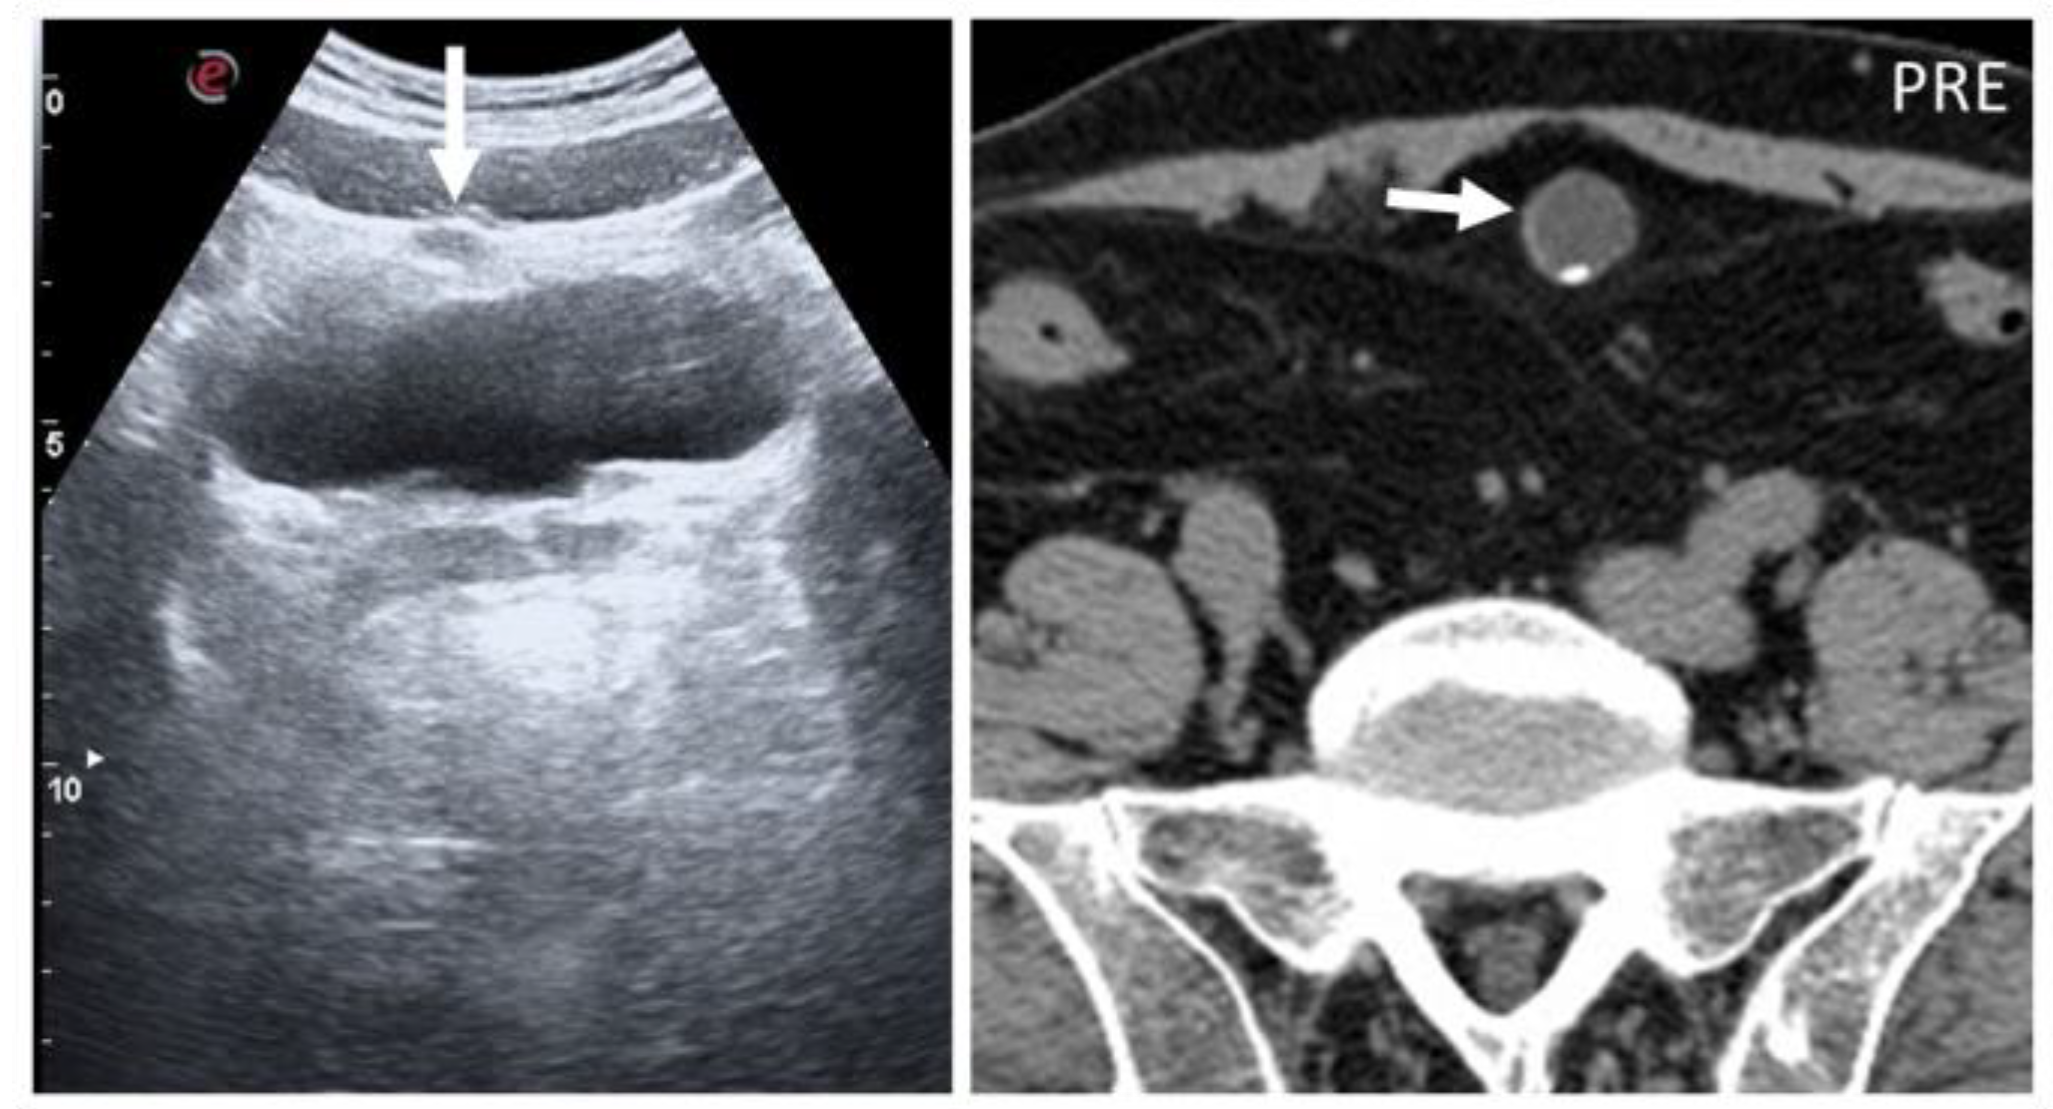

Figure 5. Urachal cysts are found along the superficial planes. On B-mode US, urachal anomalies appear as fluid-filled nodularity close to or in the context of the abdominal wall, incidentally found (arrow). As seen in axial, not-enhanced CT, small parietal calcification can also be seen (short arrow).

In the case of patent urachus, US shows a tubular structure with hypoechoic walls and anechoic content, traced along the anterior abdominal wall [18,19]. Urachal cysts are round midline, homogeneous fluid-filled structures with well-defined walls, located between the bladder and the abdominal muscles, that may contain rim calcifications [17,18,19] (Figure 5).

Umbilical–urachal sinus occurs at the umbilical end of the urachus and is seen as a fusiform outpouching structure into the abdominal wall. Imaging reveals a thickened, fusiform blind dilatation below the navel, with no communication with the bladder. Superinfection can complicate all urachal anomalies, and in that case, peripheral contrast enhancement will be seen [17]. Stone formation can complicate diverticula. Urachal remnants can degenerate into adenocarcinoma, carrying a poor prognosis due to its late presentation. The role of prophylactic surgery in these cases is still highly debated [19].